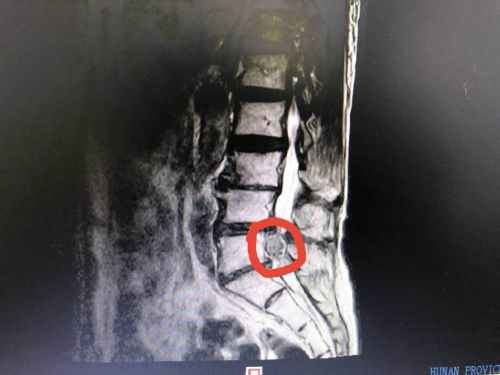

术前增强磁共振检查显示:l45椎间盘脱出游离髓核组织。

近日,脊柱外科病房收治了一位九旬高龄的梁爷爷,自述腰背部疼痛,伴右下肢麻木、疼痛一个月余,经磁共振平扫神经外科阅片后,怀疑神经源性肿瘤,脊柱外科黄象望主任医师、刘宏哲副主任医师建议做增强磁共振后,诊断为腰椎间盘突出症,最好的治疗方法是行手术治疗。